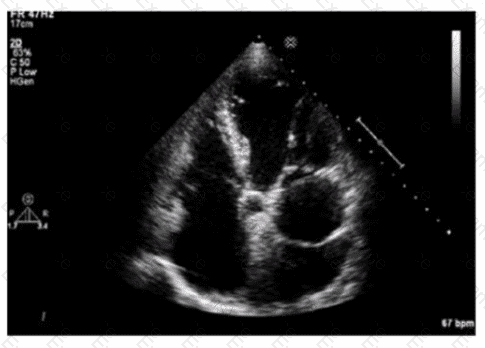

Which finding is shown in this image?